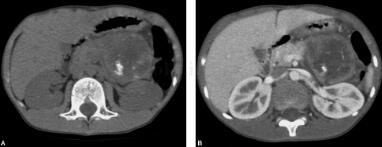

患者男,9岁。患儿4天前无明显诱因出现腹痛,以脐周及左上腹部为主,阵发性钝痛,渐渐加重,有呕吐3次,为胃内容物,非喷射状,有发热,最高达38.3℃,无腹泻,大便减少。偶有咳嗽,无气促,无惊跳,无烦吵,无抽搐,无皮疹。门诊血常规化验白细胞增高,给予抗炎治疗(具体不详),症状无好转入院治疗。自病后,食纳差,小便可,大便减少。体征:腹平坦,腹壁无红肿,未见胃肠型及腹外疝,触诊左上腹压痛、反跳痛,似可触及一包块感,触痛明显,余腹触软,无压痛,无肌紧张,叩呈鼓音,肠鸣音可闻及,3~4次/分,无气过水声。血糖、血钙、淀粉酶、AFP、CEA等均未见异常(图1)。

图1 上腹部胃、结肠脾区及胰腺体尾部之间可见一类圆形占位性病变,边界欠清,最大截面约65mm×61mm,病灶密度不均匀,壁薄,病灶内CT值2035HU,并可见点状、线状钙化影。病变与胃后壁之间可见少量液性密度影,CT值为8HU。病变与胰体尾部关系密切,胰腺形态失常,尾部增大,最大前后径约21mm,密度均匀。增强示肿块壁强化明显,其内强化不明显。胰腺头颈部形态密度正常,边界清晰,胰管未见扩张。脾动脉被向上推移,肿块邻近血管未见明确充盈缺损。肝脏、脾脏及双肾大小、形态及密度未见明显异常,胆囊大小形态未见明显异常。腹膜后未见明显肿大淋巴结